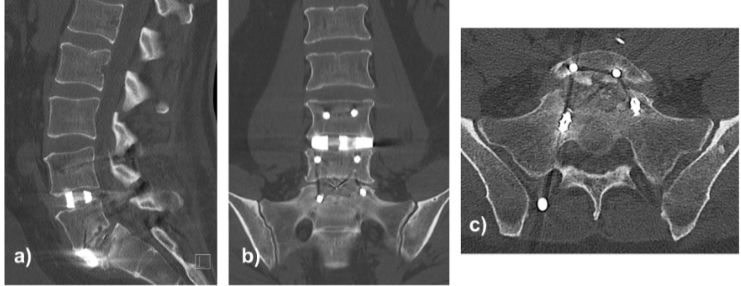

At approximately 8 weeks postoperatively, the patient developed recurrent, progressively severe right-sided lumbosciatica. CT revealed collapse of the S1 superior endplate with anterior cage subsidence, loss of indirect foraminal decompression, and recurrent L5–S1 foraminal stenosis (Fig. 5). Revision surgery included bilateral L5–S1 foraminotomies and refixation using the existing rods, with stable reconstruction achieved.

Figure 5: Lumbosacral computed tomography scan in sagittal (a), coronal (b), and axial (c) views depicting fracture of the superior endplate of S1 and anterior cage subsidence.